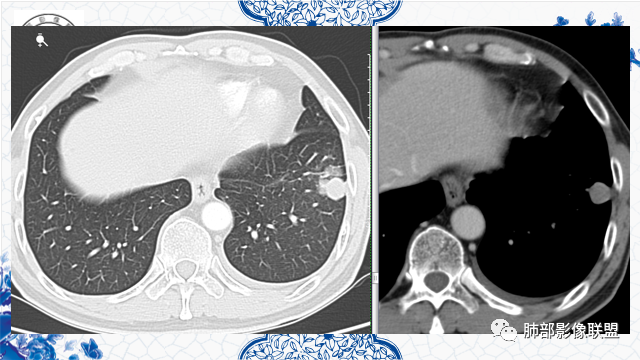

有胃肾恶性肿瘤手术史。左肺下叶胸膜下不规则肿块,部分边缘平直、部分膨隆,近端见支气管进入后截断,增强后不均匀强化,可见低密度坏死无强化,边缘见边界清楚的GGO,考虑恶性肿瘤——肺腺癌可能性大。鉴别转移瘤、鳞癌。

患者有胃肾肿瘤史,左肺下叶一不规则肿块,边界清晰,彭龙为主,靠近胸膜,有栽赃,支气管截断,内有坏死,考虑恶性腺癌可能。

发現肺占位3月,患者既往有肾、胃恶性肿瘤病史。胸部CT:左肺前外基底段近胸膜下不规则实性病灶,分叶,部分边缘平直、部分明显膨隆,内部密度不均匀,周围见磨玻璃影、边界清楚,支气管进入病灶堵塞,血管聚集,胸膜糊墙,增强扫描不均匀强化,内部多发低密度区。综合考虑恶性,转移?鉴别隐球菌、结核。

左下叶不规则实变,有平直及u型凹陷,胸膜糊墙,不均匀强化,其内可坏死灶,肿块内缘起始部可见钙化灶,病史较长,虽有胃肾肿瘤史,但影像表现及病灶走行(爬行征)均不支持转移,综合分析考虑炎性肉芽肿,OP并脓肿,其次考虑TB,留个尾巴鉴别腺癌

左肺下叶前基底段肿块,分叶状,边缘平直凹陷,部分膨隆。支气管进入后截断,宽基底与胸膜相连,内部坏死,周围有小卫星灶,强化见坏死区周围环形高密度,首先考虑良性,肉芽肿,结核?鉴别腺癌。

既往胃肾肿瘤。左下肺病灶直边,凹陷,支气管进入并有截断,宽基底与胸膜相连,内部有囊圆形坏死,旁边有卫星灶,考虑良性,肉芽肿,恶性,腺癌转移待除